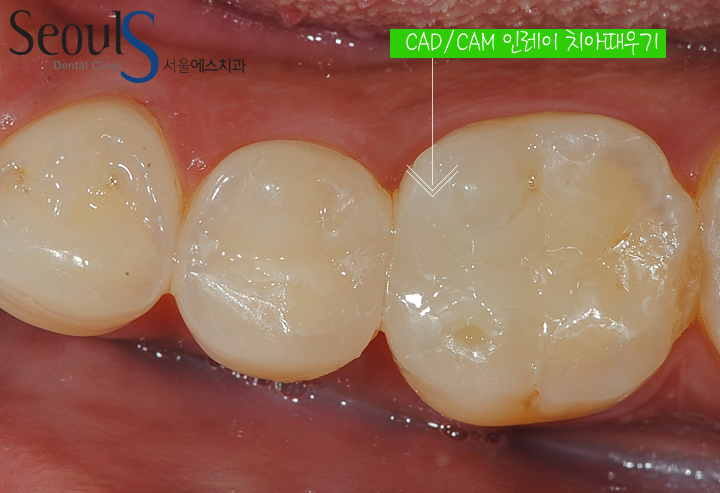

이제 본을 뜨고 CAD/CAM 인레이 제작 후 때워 치료를 마치게 됩니다

CAD/CAM 인레이로 때워 치료를 마쳤습니다

치료 전후 치아모습입니다